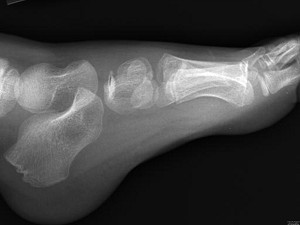

[单选题]男,28岁,踝部肿痛,结合图像,最可能的诊断是().A.未见异常B.跟骨骨髓炎C.踝关节滑膜炎D.跟骨结核E.踝关节类风湿关节炎